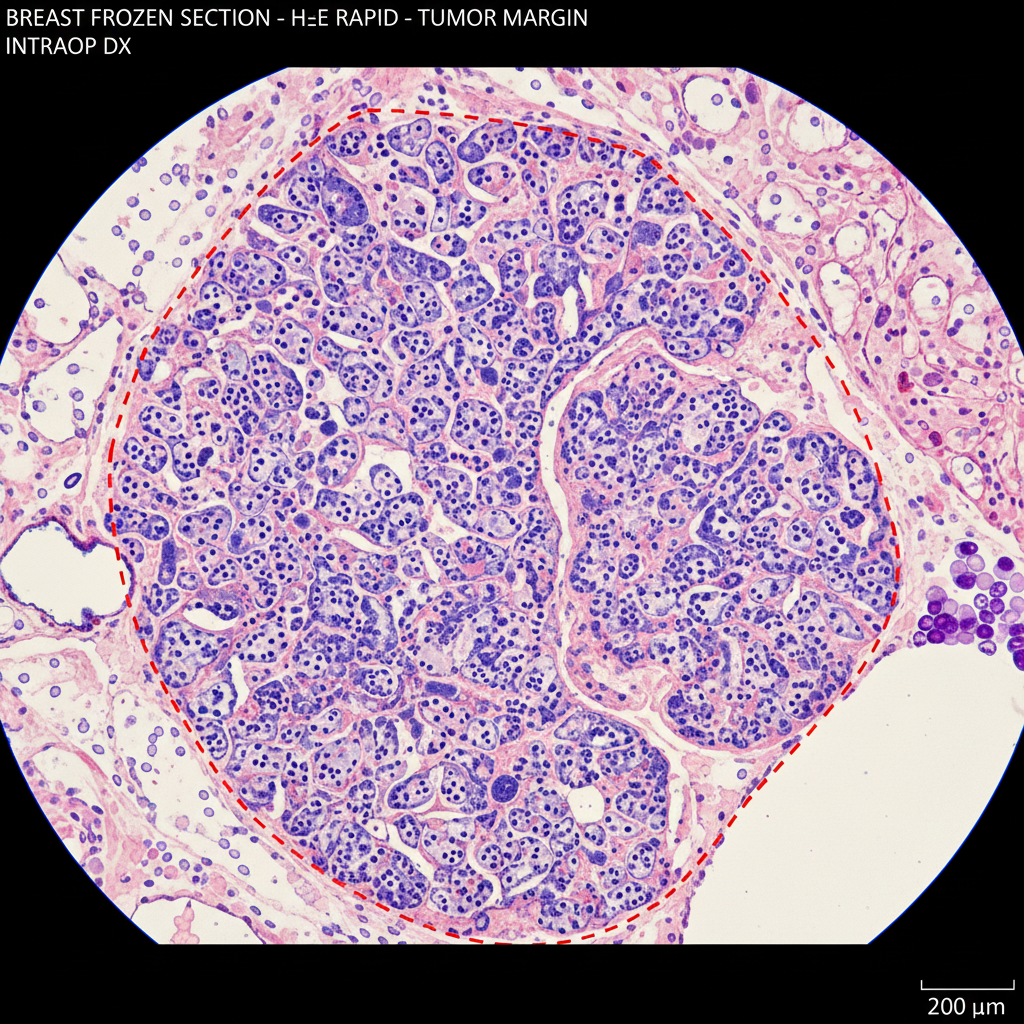

冷凍切片術中診斷快速病理手術邊緣即時診斷

拓生科技派駐資深技術人員至該院手術室旁的冷凍切片室,負責組織接收、冷凍包埋、切片、H&E 快速染色,並透過數位掃描將影像即時傳送給合作病理醫師進行遠距判讀。

- H&E 快速染色(3 分鐘完成)